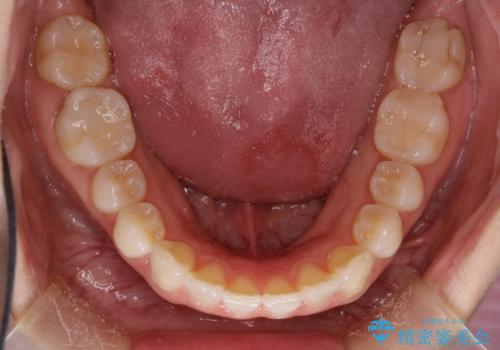

インビザラインによる矯正治療 前歯を整った歯並びへ

- 上の前歯のねじれを気にされて来院されました。

右上の前から2番目の歯が90度近くねじれて並んでいました。

こちらを当初セラミックでの治療をご希望でしたが、セラミック治療の限界と矯正治療のメリットをご説明をさせていただきました。

患者様に考えていただき、矯正治療で前歯をきれいにすることとしました。

インビザラインを使用して矯正することとしました。